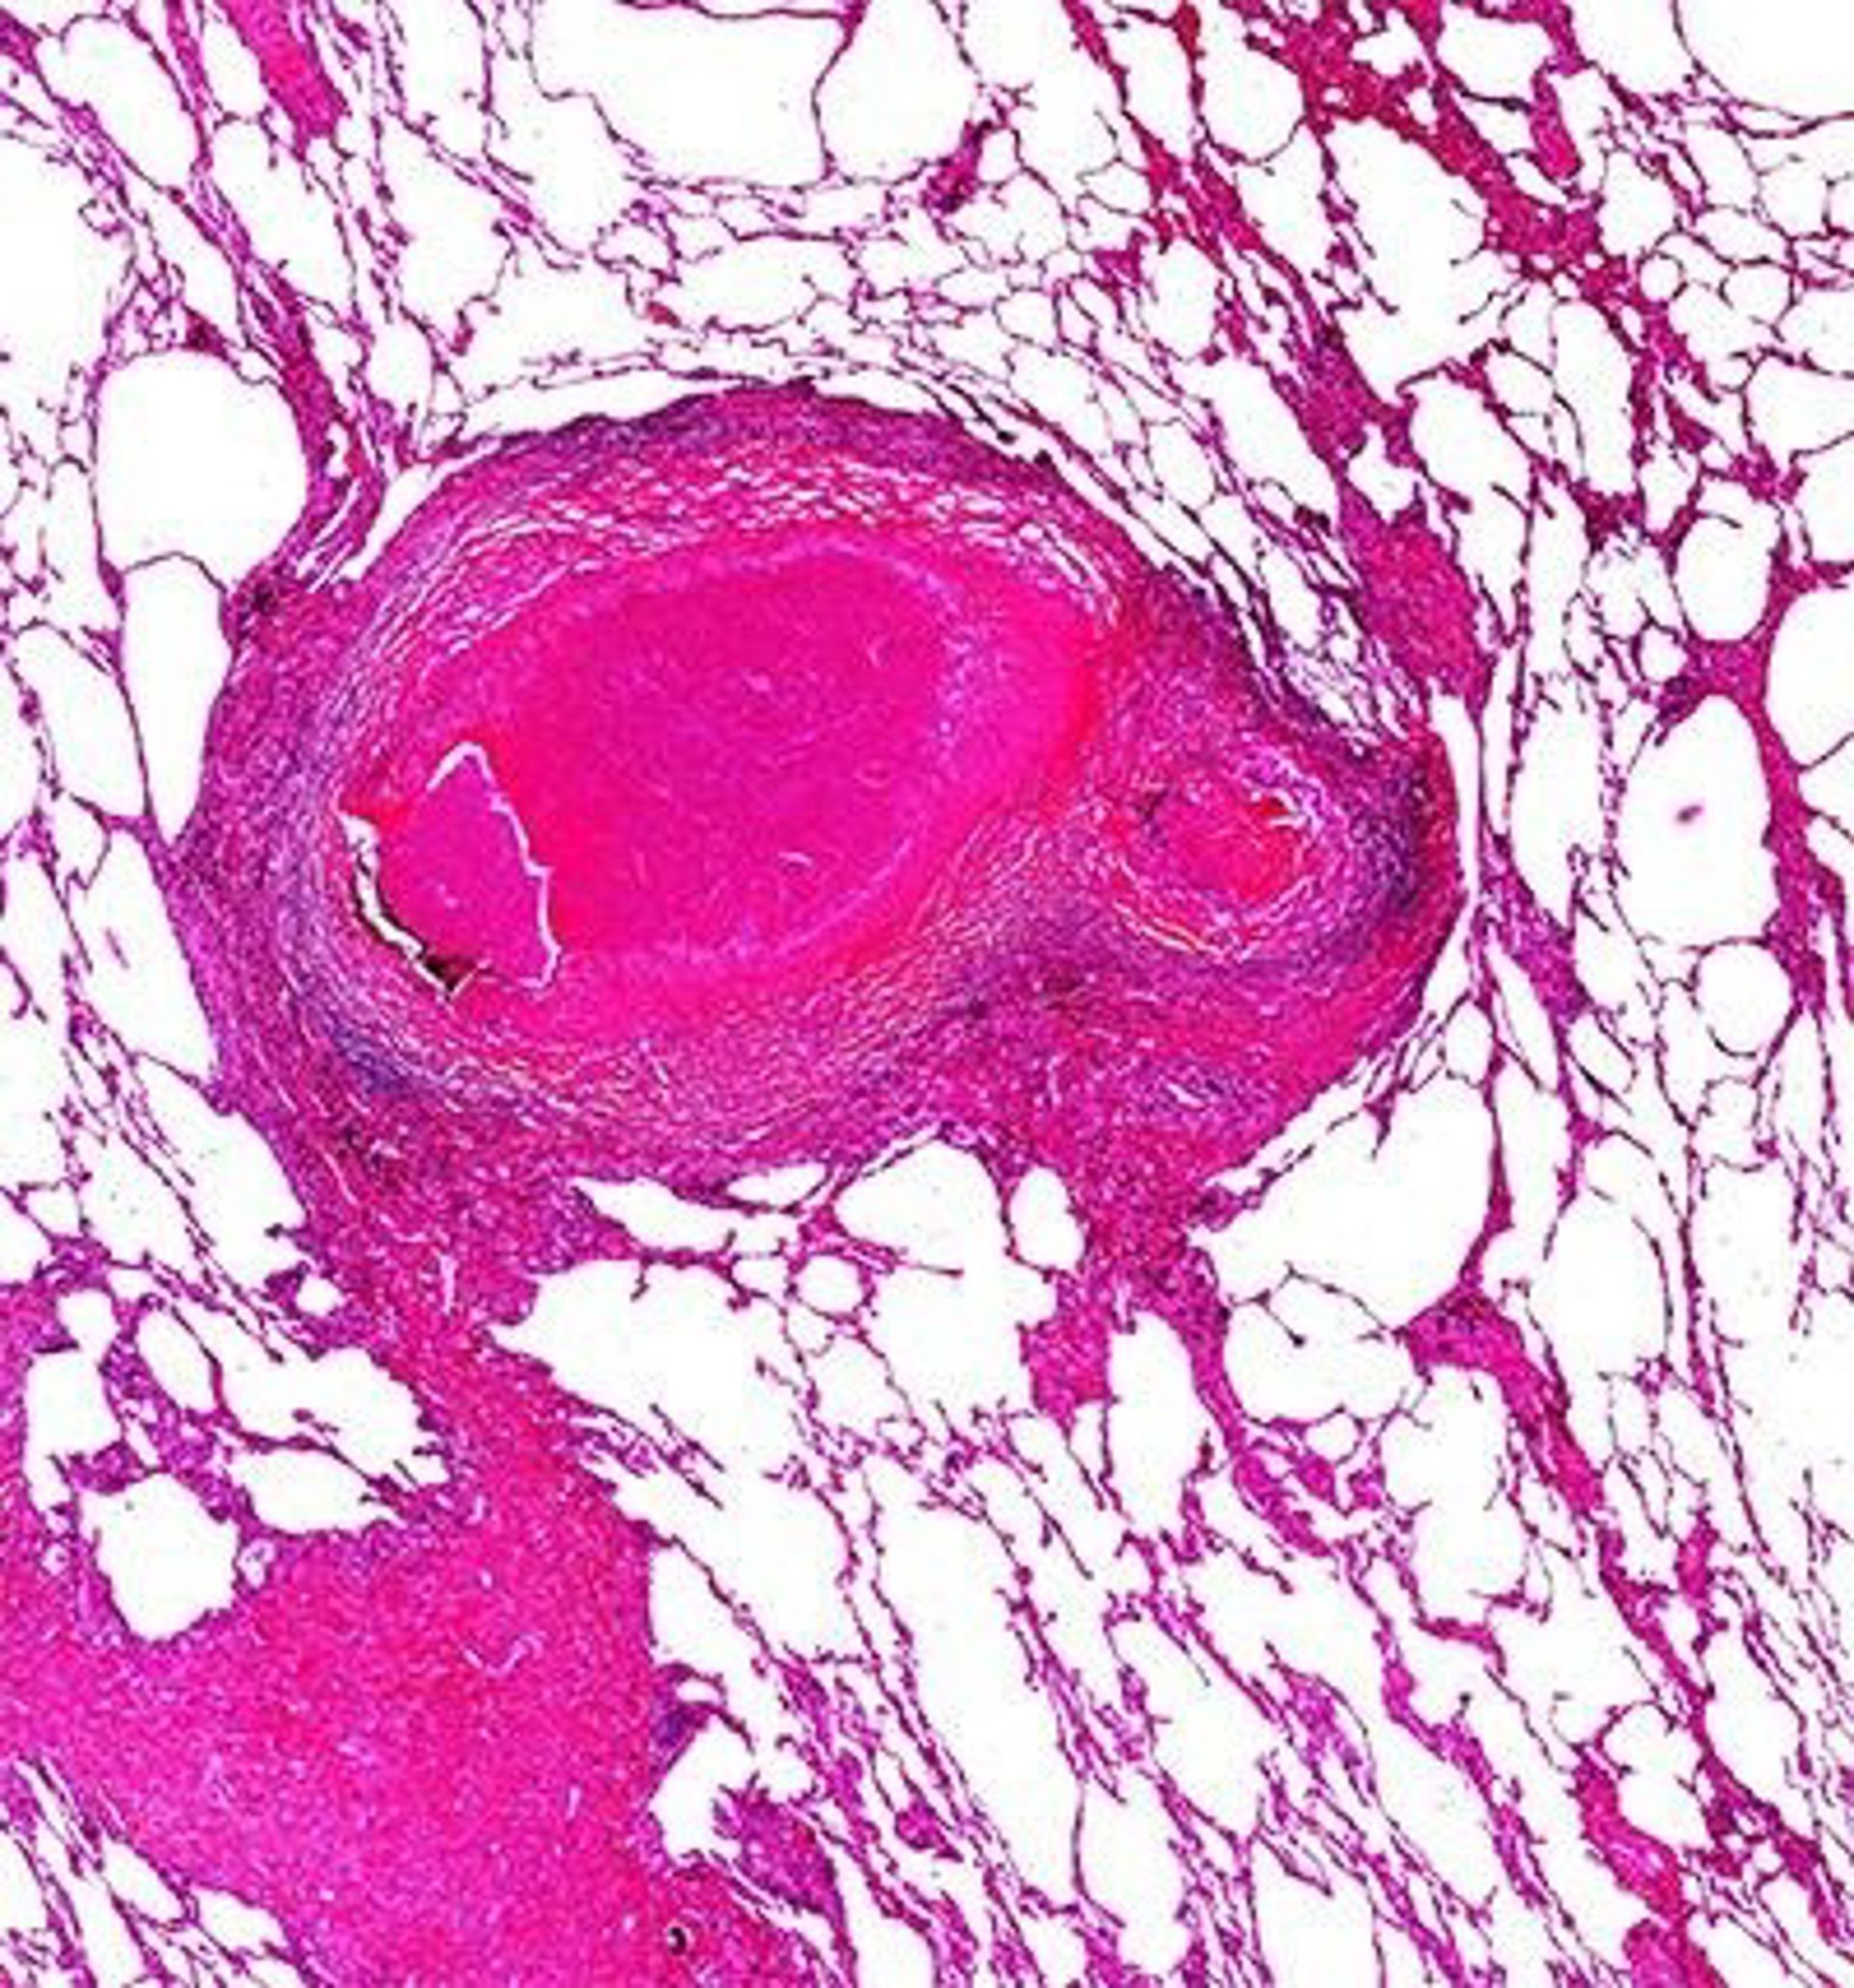

Imagen del pulmón de un enfermo de tuberculosis (Archivo)

Imagen del pulmón de un enfermo de tuberculosis (Archivo) - UAB - Archivo